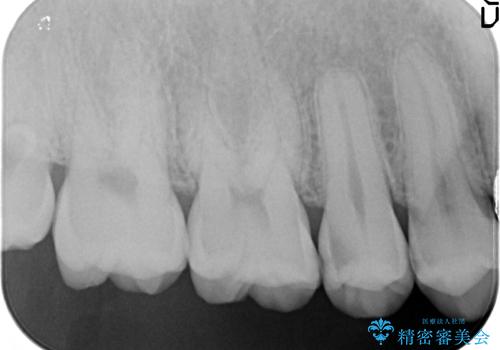

- 時々冷たいものがしみるといらした患者様です。

歯科医院に行くこと自体が久しぶりだったようで、口腔内にはたくさん虫歯がありました。

小さな虫歯に関しては保険内の白い詰め物にて、虫歯の大きい箇所はセラミックインレーにて修復しました。